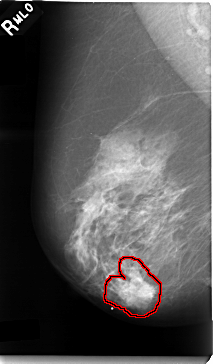

C_0006_1.LEFT_CC

FILE: C_0006_1.LEFT_CC.OVERLAY

TOTAL_ABNORMALITIES 1

ABNORMALITY 1

LESION_TYPE MASS SHAPE ARCHITECTURAL_DISTORTION MARGINS N/A

ASSESSMENT 4

SUBTLETY 1

PATHOLOGY MALIGNANT

TOTAL_OUTLINES 1

BOUNDARY